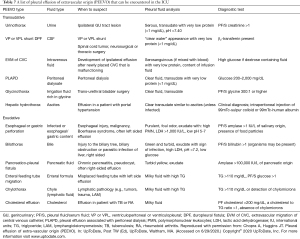

PEEVO is a rare type of pleural effusion that does not originate from the pleural vasculature and results from the migration of fluid from an extra-pleural space such as the abdomen, the genitourinary system, the biliary system, or the central nervous system (91,92). PEEVO is a rare cause of pleural effusion in critically ill patients. However, the diagnosis can be very challenging. Often patients with PEEVO undergo multiple pleural procedures before the diagnosis is made, and therefore, a high index of suspicion is needed in the appropriate clinical context. Table 7 summarizes various causes of PEEVO. Specific details of each cause of PEEVO is beyond the scope of this review (2).